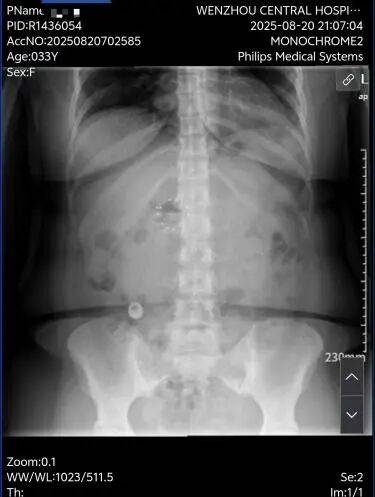

胃流转支架是一种可用于治疗肥胖症的可逆性肠道介入医疗器械。它并非传统意义上的“手术”,而是一项通过内镜(如胃镜)置入的微创治疗手段。医生在无痛胃镜下将特制支架植入胃部或十二指肠区域,改变食物在消化道中的流动路径,模拟部分胃肠道手术的效果,从而实现减重的目标。所以在8月18号经历术前的心电图及心肺功能评估,还有验血项目后,我躺在了内镜中心的手术台上,经历我30多年第一次麻醉内镜手术,在麻醉师给我带上面罩的那一下,我开始睡觉了。

而我在11月25日的时候来取出放置的胃流转支架术,手术过程也是非常的顺利,没有丝毫的痛,等麻醉过后我已经是躺在病床上挂点滴了。